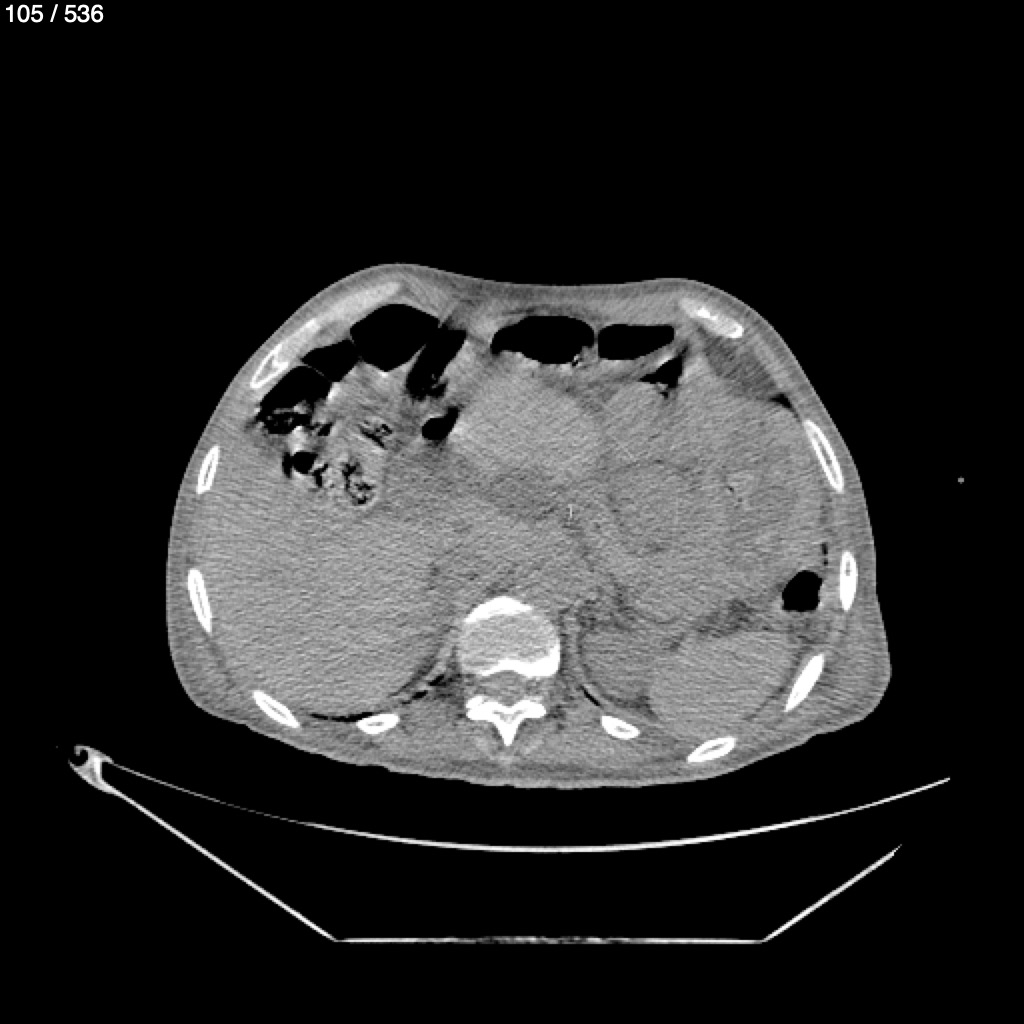

Angel Villalobos Palomeque 73 A - T.C Abdomen Simple